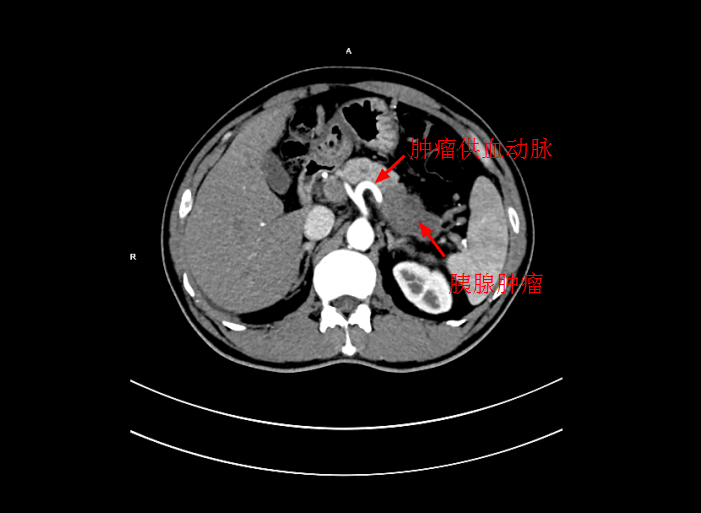

近期内三科主任李旭丹與影像科副主任胡志華攜手開展DSA下灌注化療術,治療一例局部晚期胰腺癌患者,成功将高濃度化療藥物經腫瘤的供血動脈注入到腫瘤組織中。經治療後,患者恢複良好,現已順利出院。該技術能使腫瘤組織藥物濃度達到傳統治療的10倍左右,具有殺滅腫瘤組織能力強,全身毒副作用小等優點。

患者陳某,男,49歲,2個月前出現中上腹隐痛不适,伴有腰背部疼痛,在當地醫院就診,考慮爲胃窦炎、胃窦黃斑瘤,治療後症狀未見好轉,遂來我院就診。經過檢查後,确診爲局部晚期胰腺癌,大小爲5*3cm,癌細胞已侵犯胃窦。考慮到傳統化療方式,藥物經身體多重代謝後,到達胰腺的濃度低,達不到很好殺滅腫瘤組織的效果,且對正常組織具有一定的毒副作用。爲此李旭丹主任決定給予采用DSA下介入灌注化療,得到患者及其家屬的支持。

4月30日下午,李旭丹主任與胡志華主任上台實施介入化療術,在DSA造影下,清晰可見胰腺腫瘤的供血動脈,專家們将微導管經股動脈穿刺送達瘤體的供血動脈,成功将化療藥物灌注至瘤體,順利完成手術。術後,患者症狀明顯好轉,并于5月4日順利出院。

李旭丹主任介紹,介入灌注化療,因其能準确定位腫瘤供血動脈,将藥物直接送達瘤體,能更好殺滅癌細胞,且副作用小,在胰腺癌的治療中有着非常明顯的優勢,能爲患者赢得更多的生存機會。